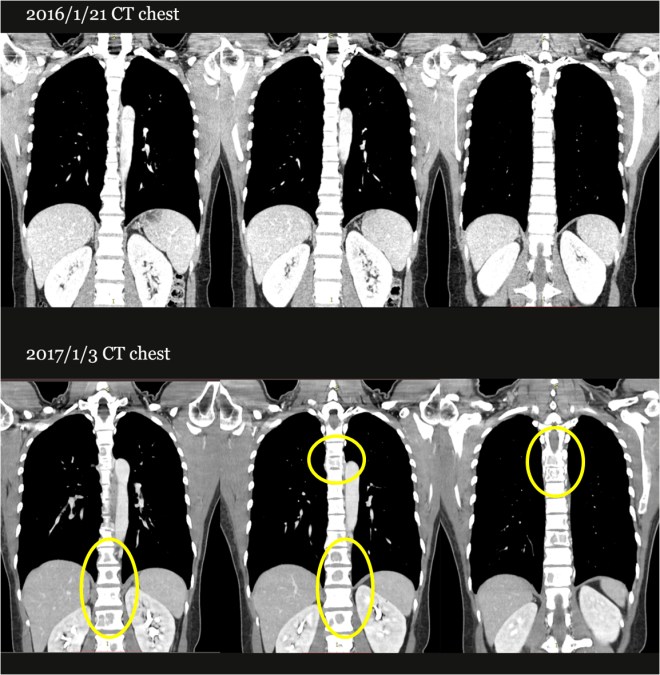

2016년 1월 유방암 초기 발견 때부터 PET 사진에서 보듯이 사나워 보이는 다발적인 유방암이 발견되었고  이후 소양인에게 않은 쑥뜸 등 치료를 받으면서 악화되어서 통증과 뼈전이 후에 더 이상 통증제어가 안되자 다시금 요꼬 선생님을 찾아왔고, 이후 나에게 치료를 2017년 1월 5일부터 시작하였다.

강정주2-1-000.jpg

위의 CT image에서 보듯이 2017년 1월 3일흉추와 요추에 보이던 뼈전이(bone metastasis )로 보이던 검은 음영들이  2017년 5월 24일 사진에서는 많이 엷어진 것이 눈에 띈다.

또한 CT 에서 보듯이  2016년 1월에 척추에 보이지 않던 종양이 1년 뒤인 2017년 1월 사진을 보면 여러 군데 검은 점으로 표시되는 곳에 보이게 되었다. 환자는 극심한 뼈에서부터 유발되는 통증을 여러 군데 느끼게 되었고 숨도 잘 쉬지 못하게 되었다.